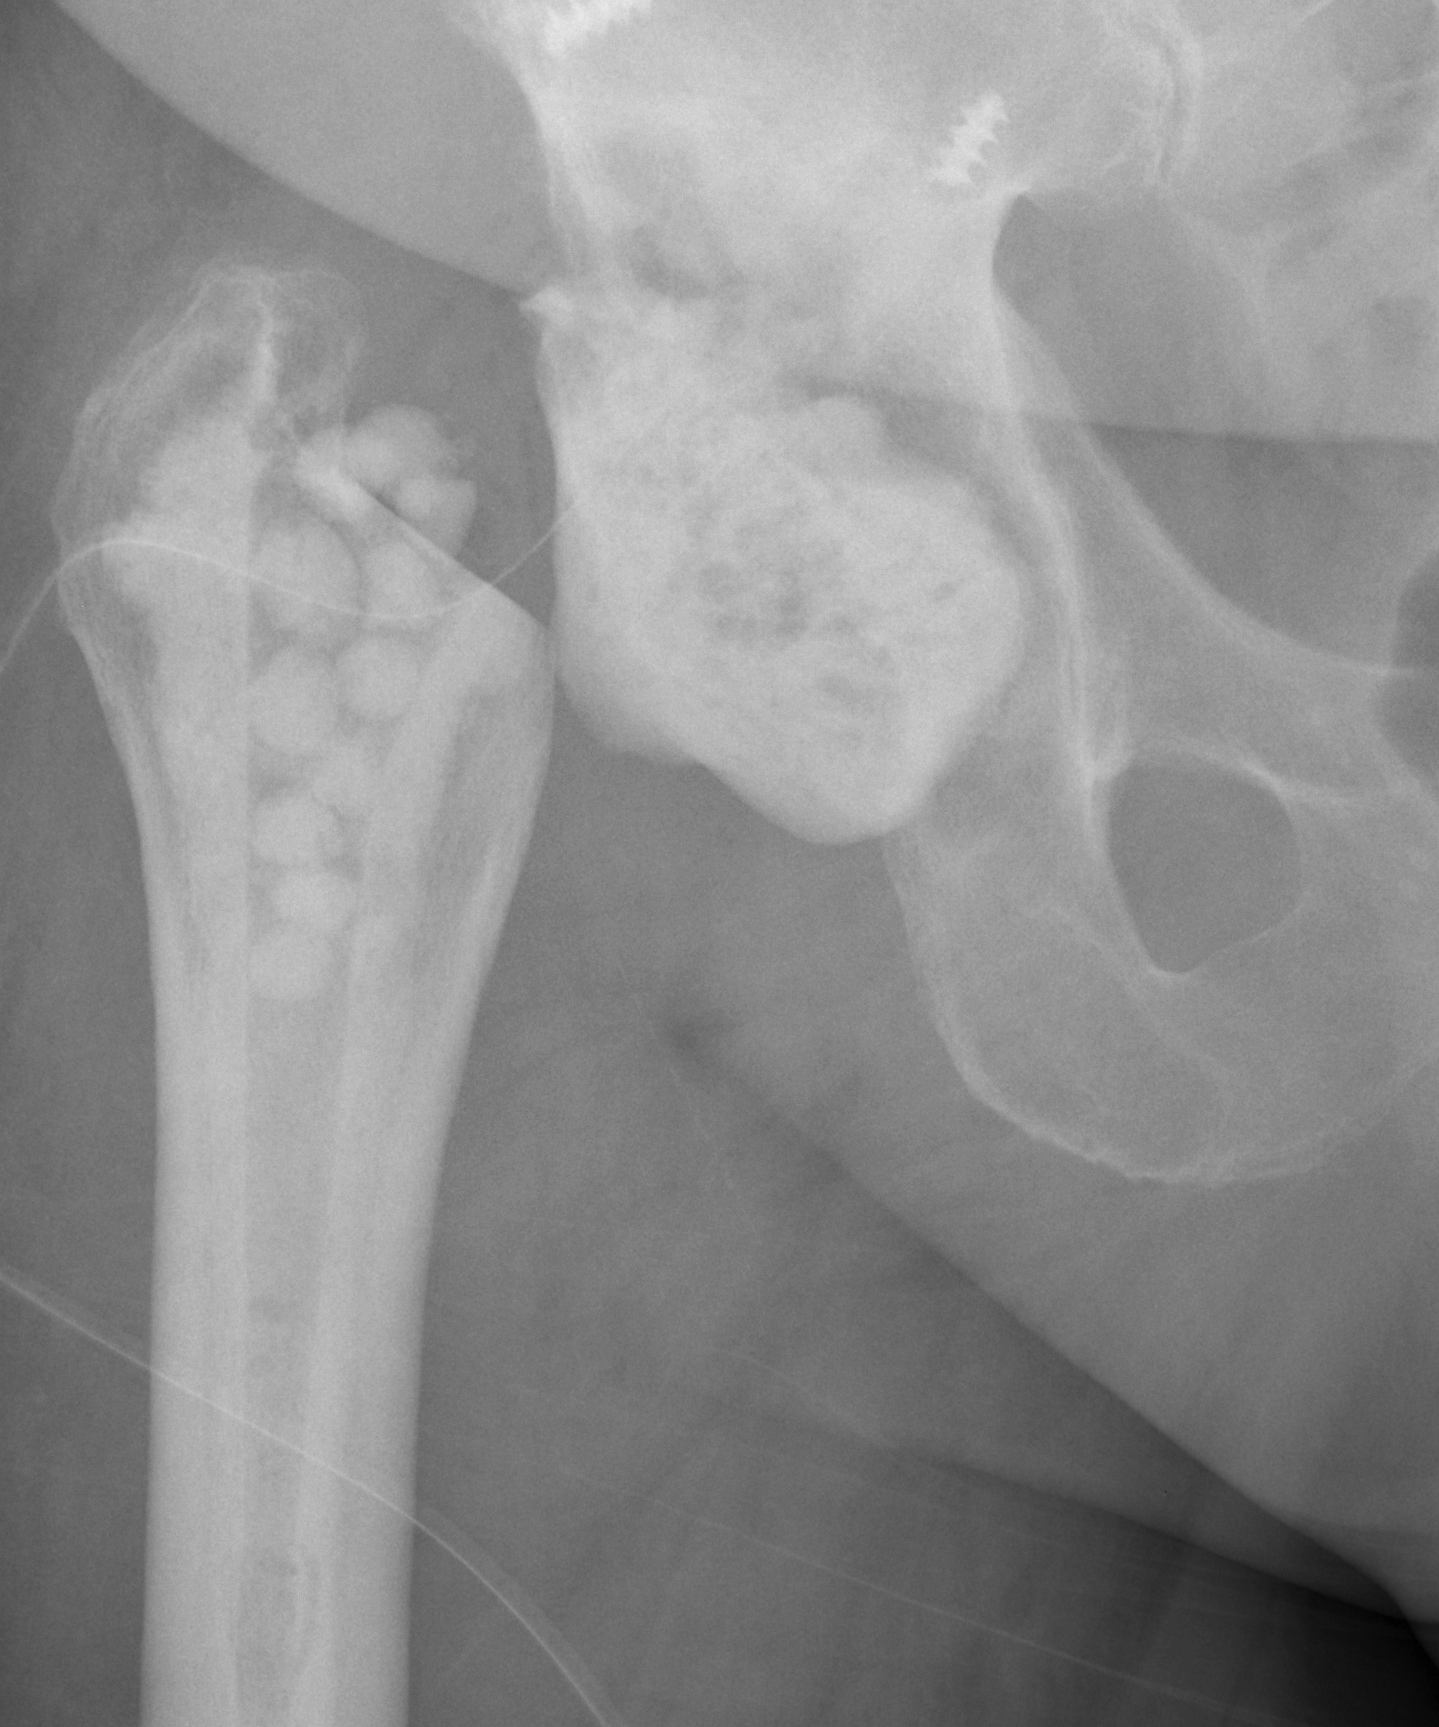

Resection Arthroplasty / Girdlestone

Indications

- medically unfit for further revision surgery

- refusal for further revision surgery

- sepsis control / virulent bug

- unrevisable due to bone loss

- unlikely to become mobile

Advantage

Effective control of infection (95%)

Disadvantage

Poor function

- pain / limp

- require walking aid

- 5cm average LLD